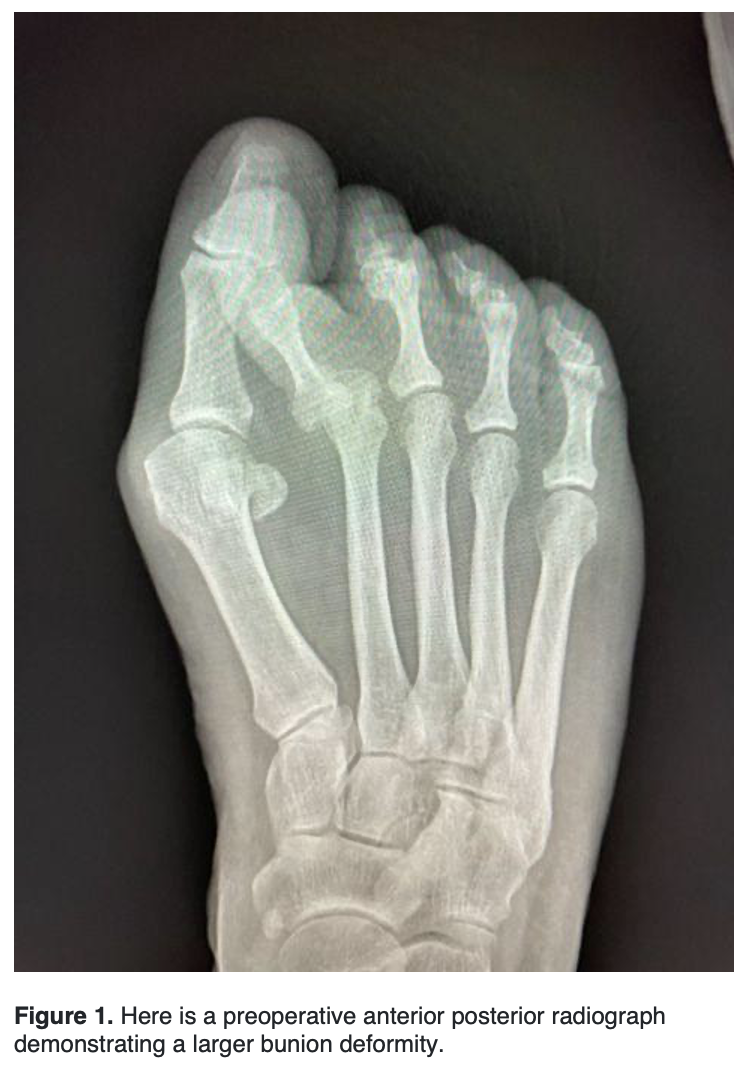

With advancing technology, new emerging bunion techniques have evolved, the newest concept being innovations in minimally invasive surgery (MIS). The question, however, is, “What procedure should surgeons do for a larger bunion deformity?”

Traditionally, surgeons used the Lapidus and proximal osteotomies of the first metatarsal to correct larger bunion deformities. In the last several years, it has become increasingly common to correct larger bunion deformities with distal MIS osteotomies. Here, the authors review the current literature on correcting larger bunion deformities with both Lapidus and MIS techniques.

Severe hallux valgus is categorized as an intermetatarsal (IM) angle of greater than or equal to 20 degrees and a hallux valgus angle (HAV) of greater than 40 degrees.